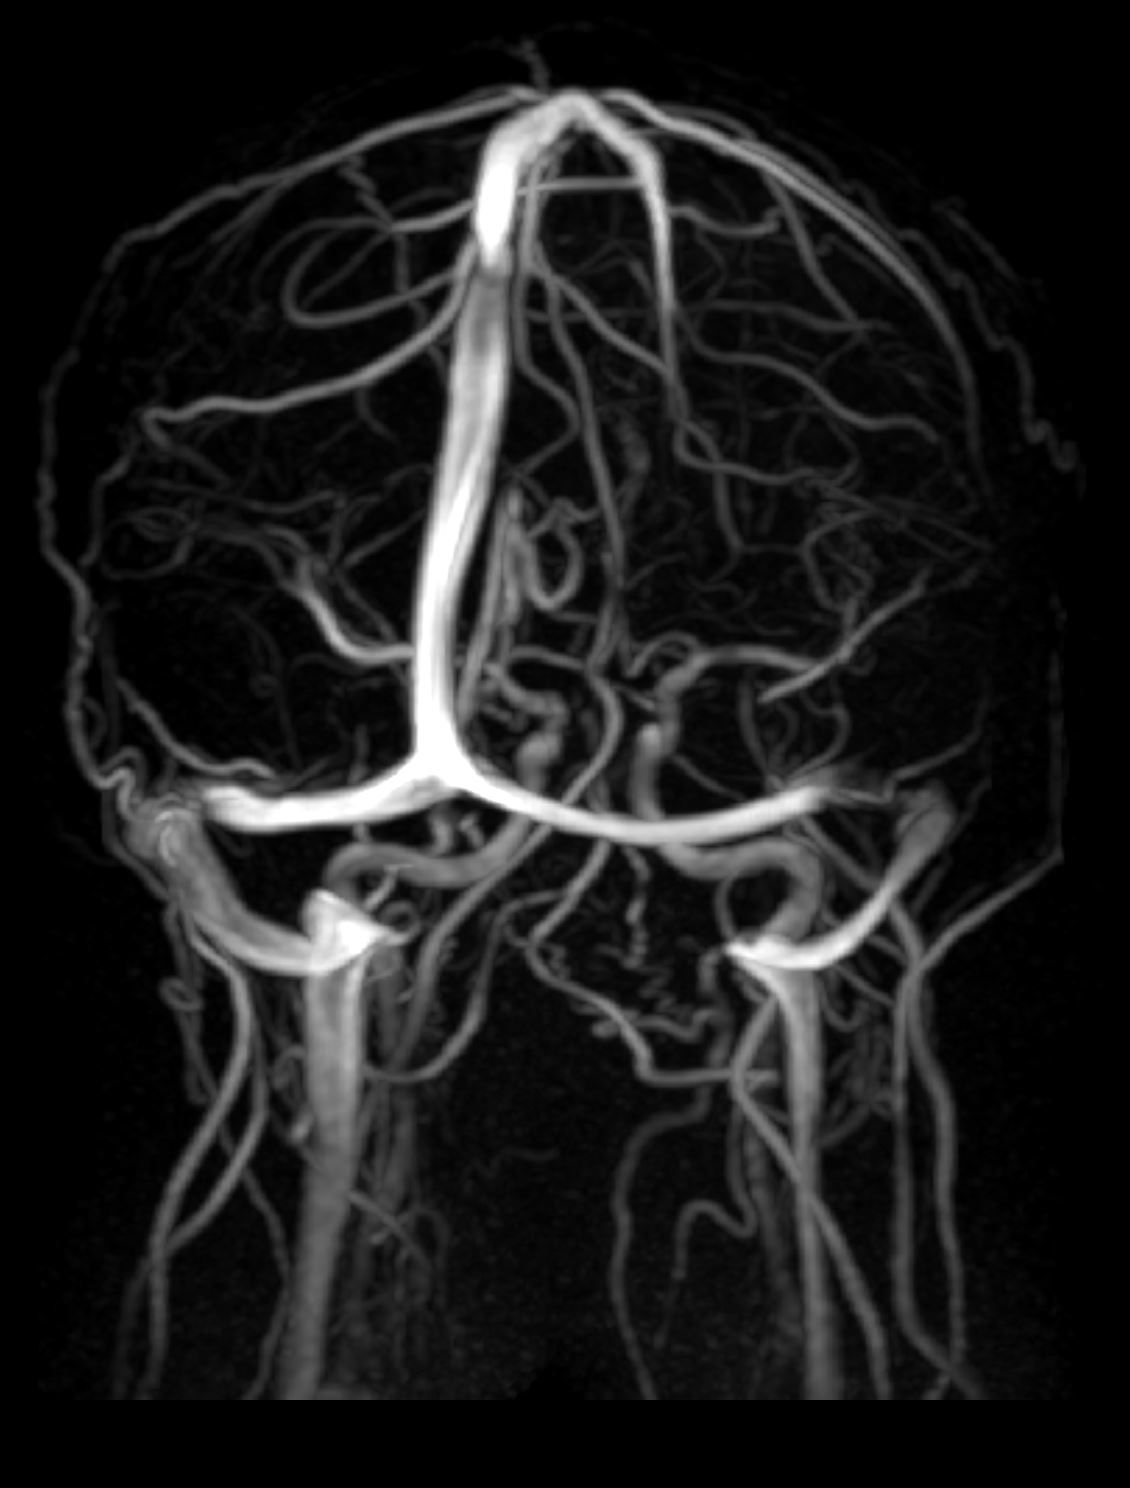

Image IQ Quiz: 25-Year-Old Male with a Headache

What do the images reveal in a 25-year-old male with a headache?